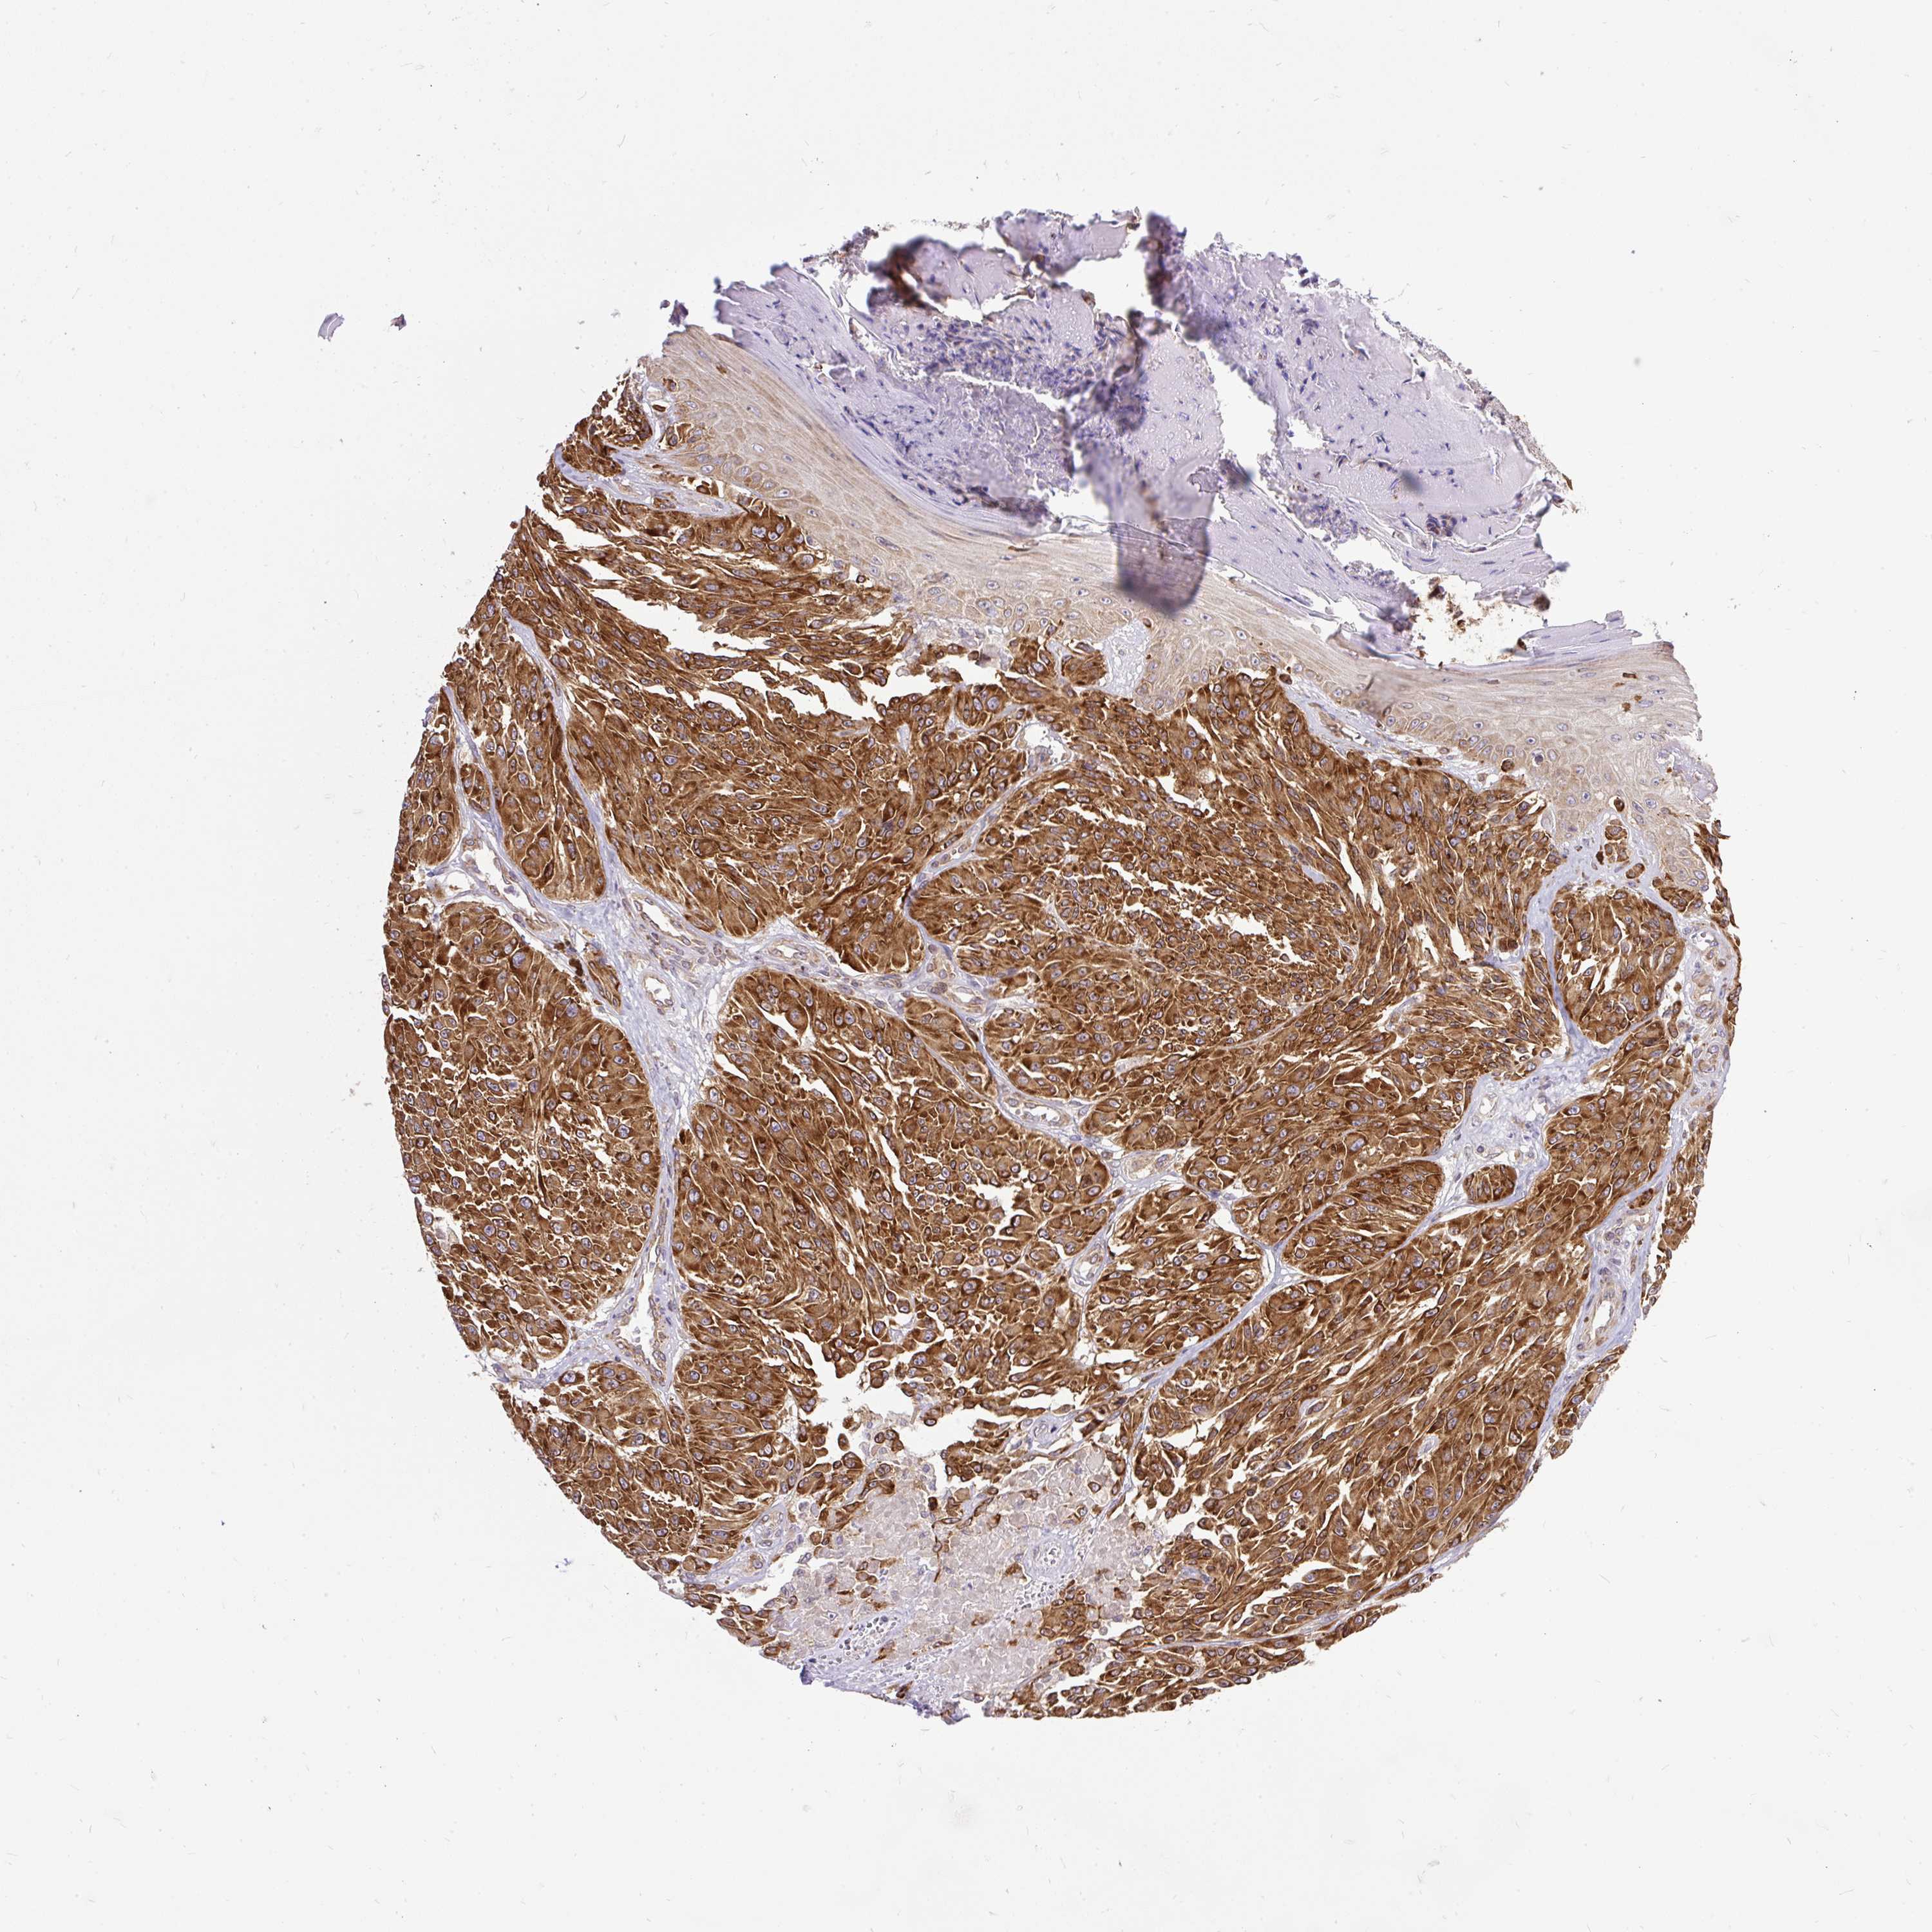

MELANOMA - Protein expressioni

A mouse-over function shows sample information and annotation data. Click on an image to view it in a full screen mode. Samples can be filtered based on level of antibody staining by selecting one or several of the following categories: high, medium, low and not detected. The assay and annotation is described here.

Note that samples used for immunohistochemistry by the Human Protein Atlas do not correspond to samples in the TCGA dataset.

Antibody stainingi

Antibody staining in the annotated cell types in the current human tissue is reported as not detected, low, medium, or high, based on conventional immunohistochemistry profiling in selected tissues. This score is based on the combination of the staining intensity and fraction of stained cells.

Each image is clickable and will lead to virtual microscopy that enables deeper exploration of all samples and also displays staining intensity scores, fraction scores and subcellular localization as well as patient and tissue information for each sample.

Antibody HPA054908

Staining

High

Medium

Low

Not detected

Intensity

Strong

Moderate

Weak

Negative

Quantity

>75%

75%-25%

<25%

None

Location

Nuclear

Cytoplasmic/membranous

Cytoplasmic/membranous,nuclear

Malignant melanoma, Metastatic site

Malignant melanoma, NOS